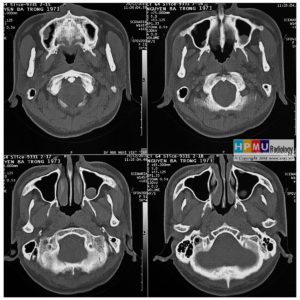

Chấn thương hàm mặt

Lượt xem: 275» 01-11-2018 -

Chấn thương hàm mặt

Lượt xem: 180» 01-11-2018 -